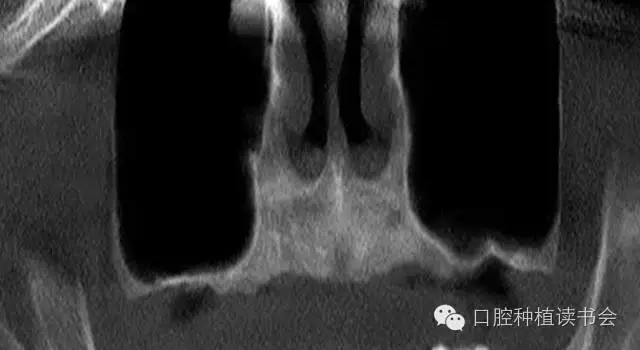

雖然牙槽脊垂直、水平吸收的程度幾乎相當,但是由于上頜后牙牙槽脊寬度較大,后牙區(qū)經(jīng)常出現(xiàn)圓鈍的、較寬的牙槽骨狀態(tài),臨床表現(xiàn)為剩余牙槽骨高度(Residual Bone Height,RBH)不足。在個別情況下,由于嚴重牙周病、根尖病等因素的影響,也會使牙槽脊水平寬度不足,表現(xiàn)為刃狀牙槽脊。上頜后牙一般為多根牙,當牙周病和根尖病到一定程度后,磨牙才開始松動導致不能保留,又因上頜牙槽骨骨密度較低,在有些病例,牙槽脊重度吸收,RBH甚至不足1mm(圖1)。

▲(圖1)